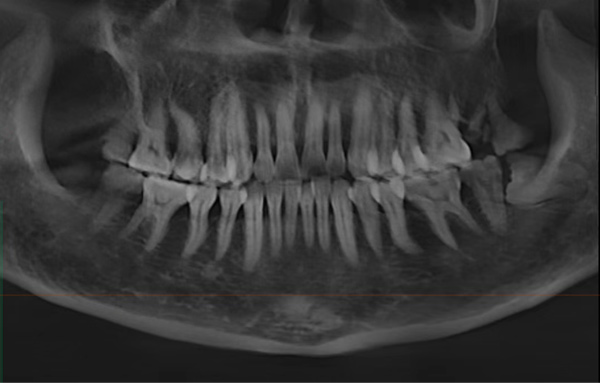

“最开始她以为是之前治疗过的那颗牙(右上第一前磨牙)又出问题了,但我们仔细检查后发现,真正让她痛得睡不着的是另一颗快被蛀空的大牙(右上颌第二磨牙)。”黄医生回忆道,“那颗牙表面已经蛀得不成样子,一碰冷水就疼得直抽气,轻轻敲击也疼得厉害。当时她特别担心要反复治疗,我们就商量着把两颗邻近的牙一起做了根管治疗,也避免她来回奔波。”